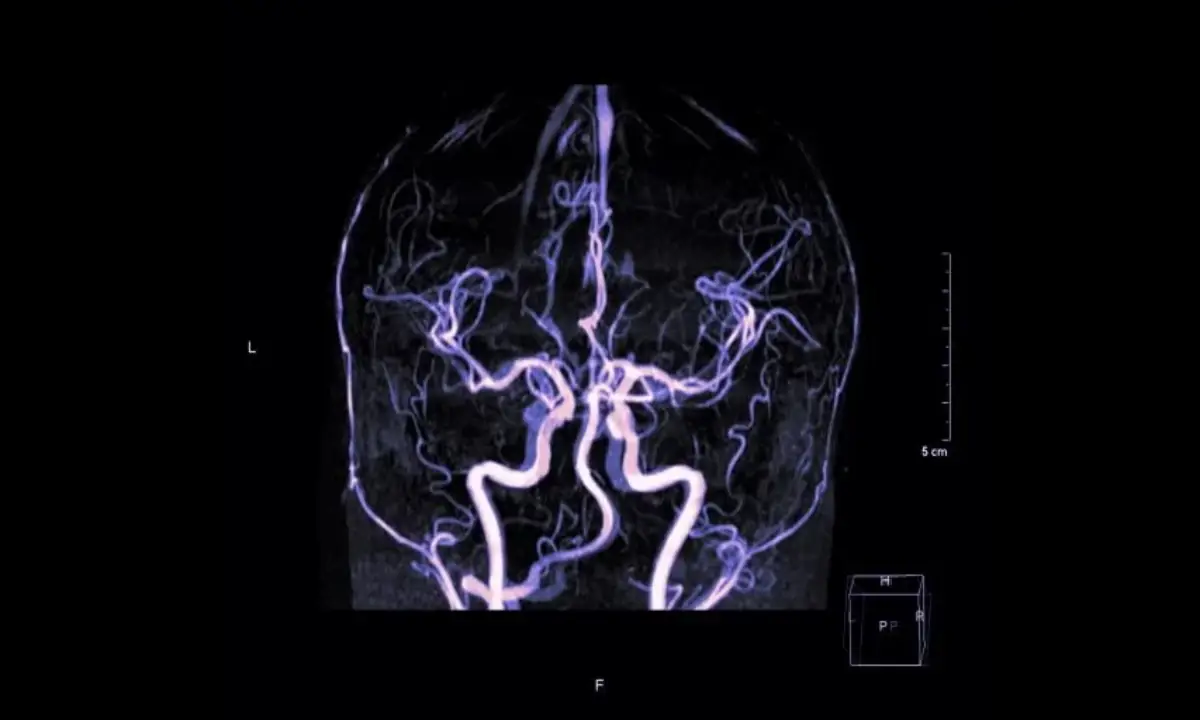

تشخیص آنوریسم مغزی، به خصوص قبل از پارگی، اغلب با استفاده از تکنیکهای تصویربرداری پیشرفته انجام میشود. اگر فردی با علائم پارگی آنوریسم به اورژانس مراجعه کند، اولین اقدام معمولاً سیتی اسکن مغز برای تشخیص خونریزی است. در مواردی که سیتی اسکن طبیعی است اما شک بالینی به خونریزی وجود دارد، ممکن است آزمایش مایع مغزی-نخاعی انجام شود.

برای مشاهده دقیقتر خود آنوریسم، از روشهایی مانند “آنژیوگرافی سیتی اسکن” (CTA) یا “آنژیوگرافی تشدید مغناطیسی” (MRA) استفاده میشود. با این حال، استاندارد طلایی برای تجسم دقیق آنوریسم، “آنژیوگرافی تفریقی دیجیتال” (DSA) است. در این روش، یک کاتتر نازک از طریق یک شریان در کشاله ران به سمت رگهای مغز هدایت شده و با تزریق ماده حاجب، تصاویر دقیقی از عروق مغزی تهیه میشود.